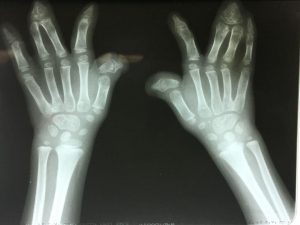

Las lesiones en las manos son comunes y pueden ocasionar un tiempo de inactividad prolongado. Para analizar e identificar los factores que afectan el tiempo de trabajo, se necesita una visión holística de los pacientes. La Clasificación Internacional del Funcionamiento, la Discapacidad y la Salud (ICF) de la Organización Mundial de la Salud con su perspectiva biopsicosocial brinda una visión tan holística. El propósito de este estudio es analizar el tiempo de ausencia de trabajo en pacientes con lesiones traumáticas en las manos e identificar los factores que afectan el tiempo libre del trabajo desde una perspectiva biopsicosocial.

En total, se incluyeron 231 participantes del estudio con una amplia gama de lesiones en las manos. De estos, 178 pacientes (77%) regresaron al trabajo en 200 días. Las deficiencias en la movilidad de las funciones de la articulación y las funciones sensoriales relacionadas con la temperatura y otros estímulos, así como una mayor tensión de la mano en el trabajo, condujeron a un tiempo de inactividad prolongado. El género, el buen uso de la mano y el estado laboral también influyeron en el tiempo de descanso en los submodelos. Nuestros resultados demuestran que se recomienda una perspectiva biopsicosocial cuando se investiga el tiempo de inactividad prolongado.